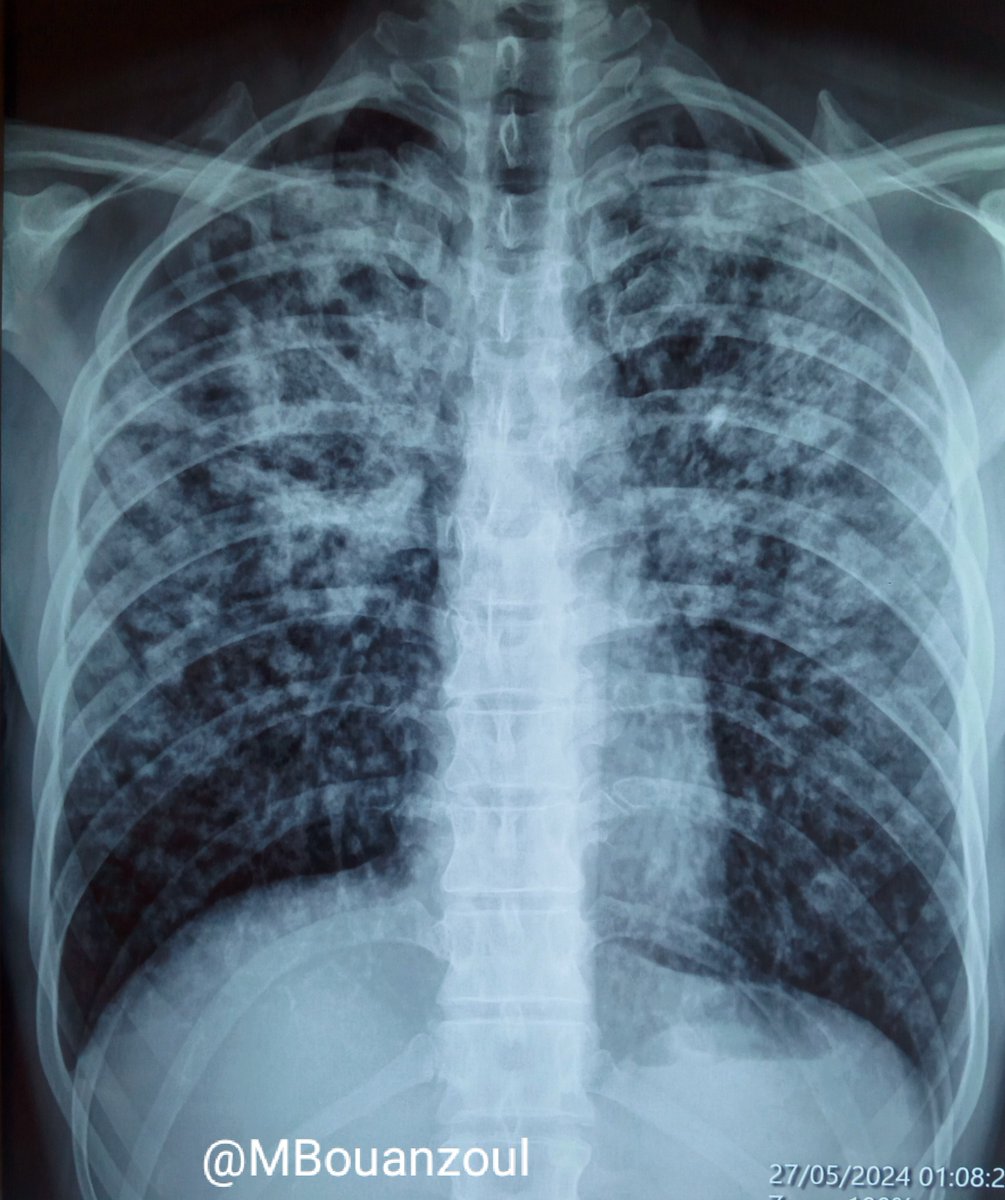

Sharing a chest radiograph of a pulmonary tuberculosis in a 42-year-old man presenting with cough and malaise. Rapid sputum exam was positive. HIV testing was negative. #tuberculosis #chestrad #PulmCCM #radres